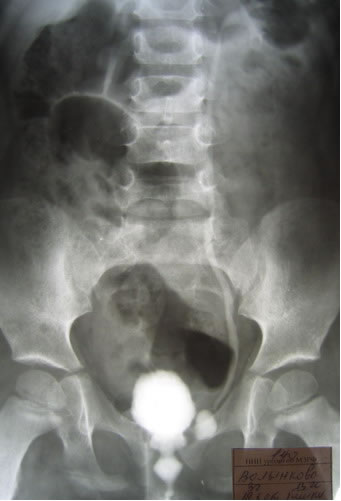

Экскреторная урография

Цистография